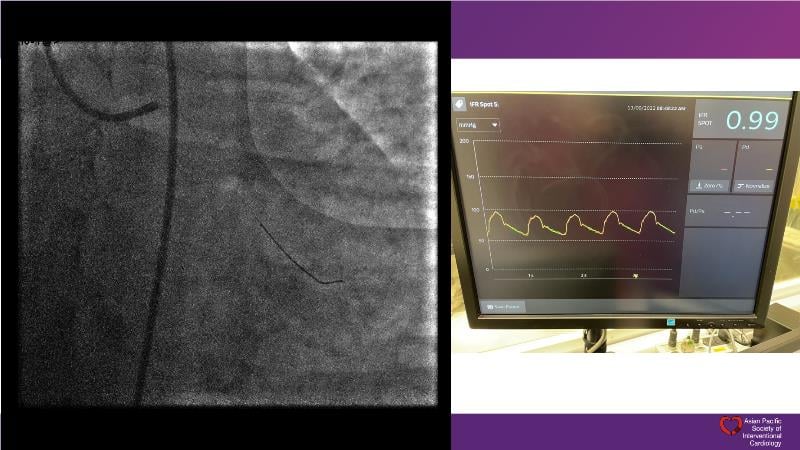

Consult this session to understand the technology and scientific evidence of the novel sirolimus drug-coated balloon, to learn its utility for PCI in a variety of lesion and patient subsets and to understand the evidence and outcomes in real-world patients.

- To understand the technology and scientific evidence of the novel sirolimus drug-coated balloon (SDCB)

- To learn the utility of the DCB for PCI in a variety of lesion and patient subsets

- To understand the evidence and outcomes of this DCB in real world patients